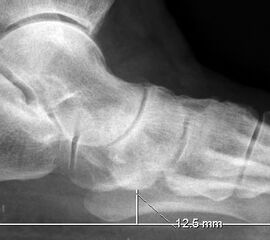

„Cuneiforme height“ (Abb. 6f)

Auf der seitlichen, stehenden Aufnahme des Fußes wird ebenfalls der laterale Talo-Metatarsale I Winkel (Abb. 6 d) gemessen und so das kollabierte mediale Längsgewölbe dokumentiert. Auch hier gilt ein Talo-Metatarsale I Winkel von > 5° (nach plantar konvex) als pathologisch 21. Der Kollaps findet dabei meist im Talonaviculargelenk, seltener in der Naviculocuneiform-Gelenkreihe statt. Instabilität und Arthrose im 1. TMT sollten ausgeschlossen oder bei der Operationsplanung mit einbezogen werden. Weitere wichtige radiologische Messungen zur Beurteilung der Planovalgus-Statik und Progression der Deformität sind der laterale talo-calcaneare Winkel (Abb. 6 e) und der Abstand des Os cuneiforme-Unterrandes zum Untergrund (Abb. 6 f, Cuneiform height, 22. Eine anteriore Translation des Talus auf dem Kalkaneus findet man sowohl auf der ap, als auch auf der seitlichen Aufnahme des Fuβes mit Aufhebung der Cima-Linie.